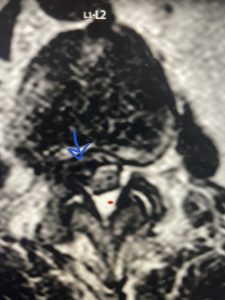

(Figs 5a): Sagittal (a) and axial (b) T2-weighted lumbar MRI demonstrating status post lumbar decompression and insitu fusion L2-5 now well decompressed (blue dash) with development of new (red arrow) severe stenosis and with superimposed right L1-2 disc herniation (blue arrow)

(Figs 5b)